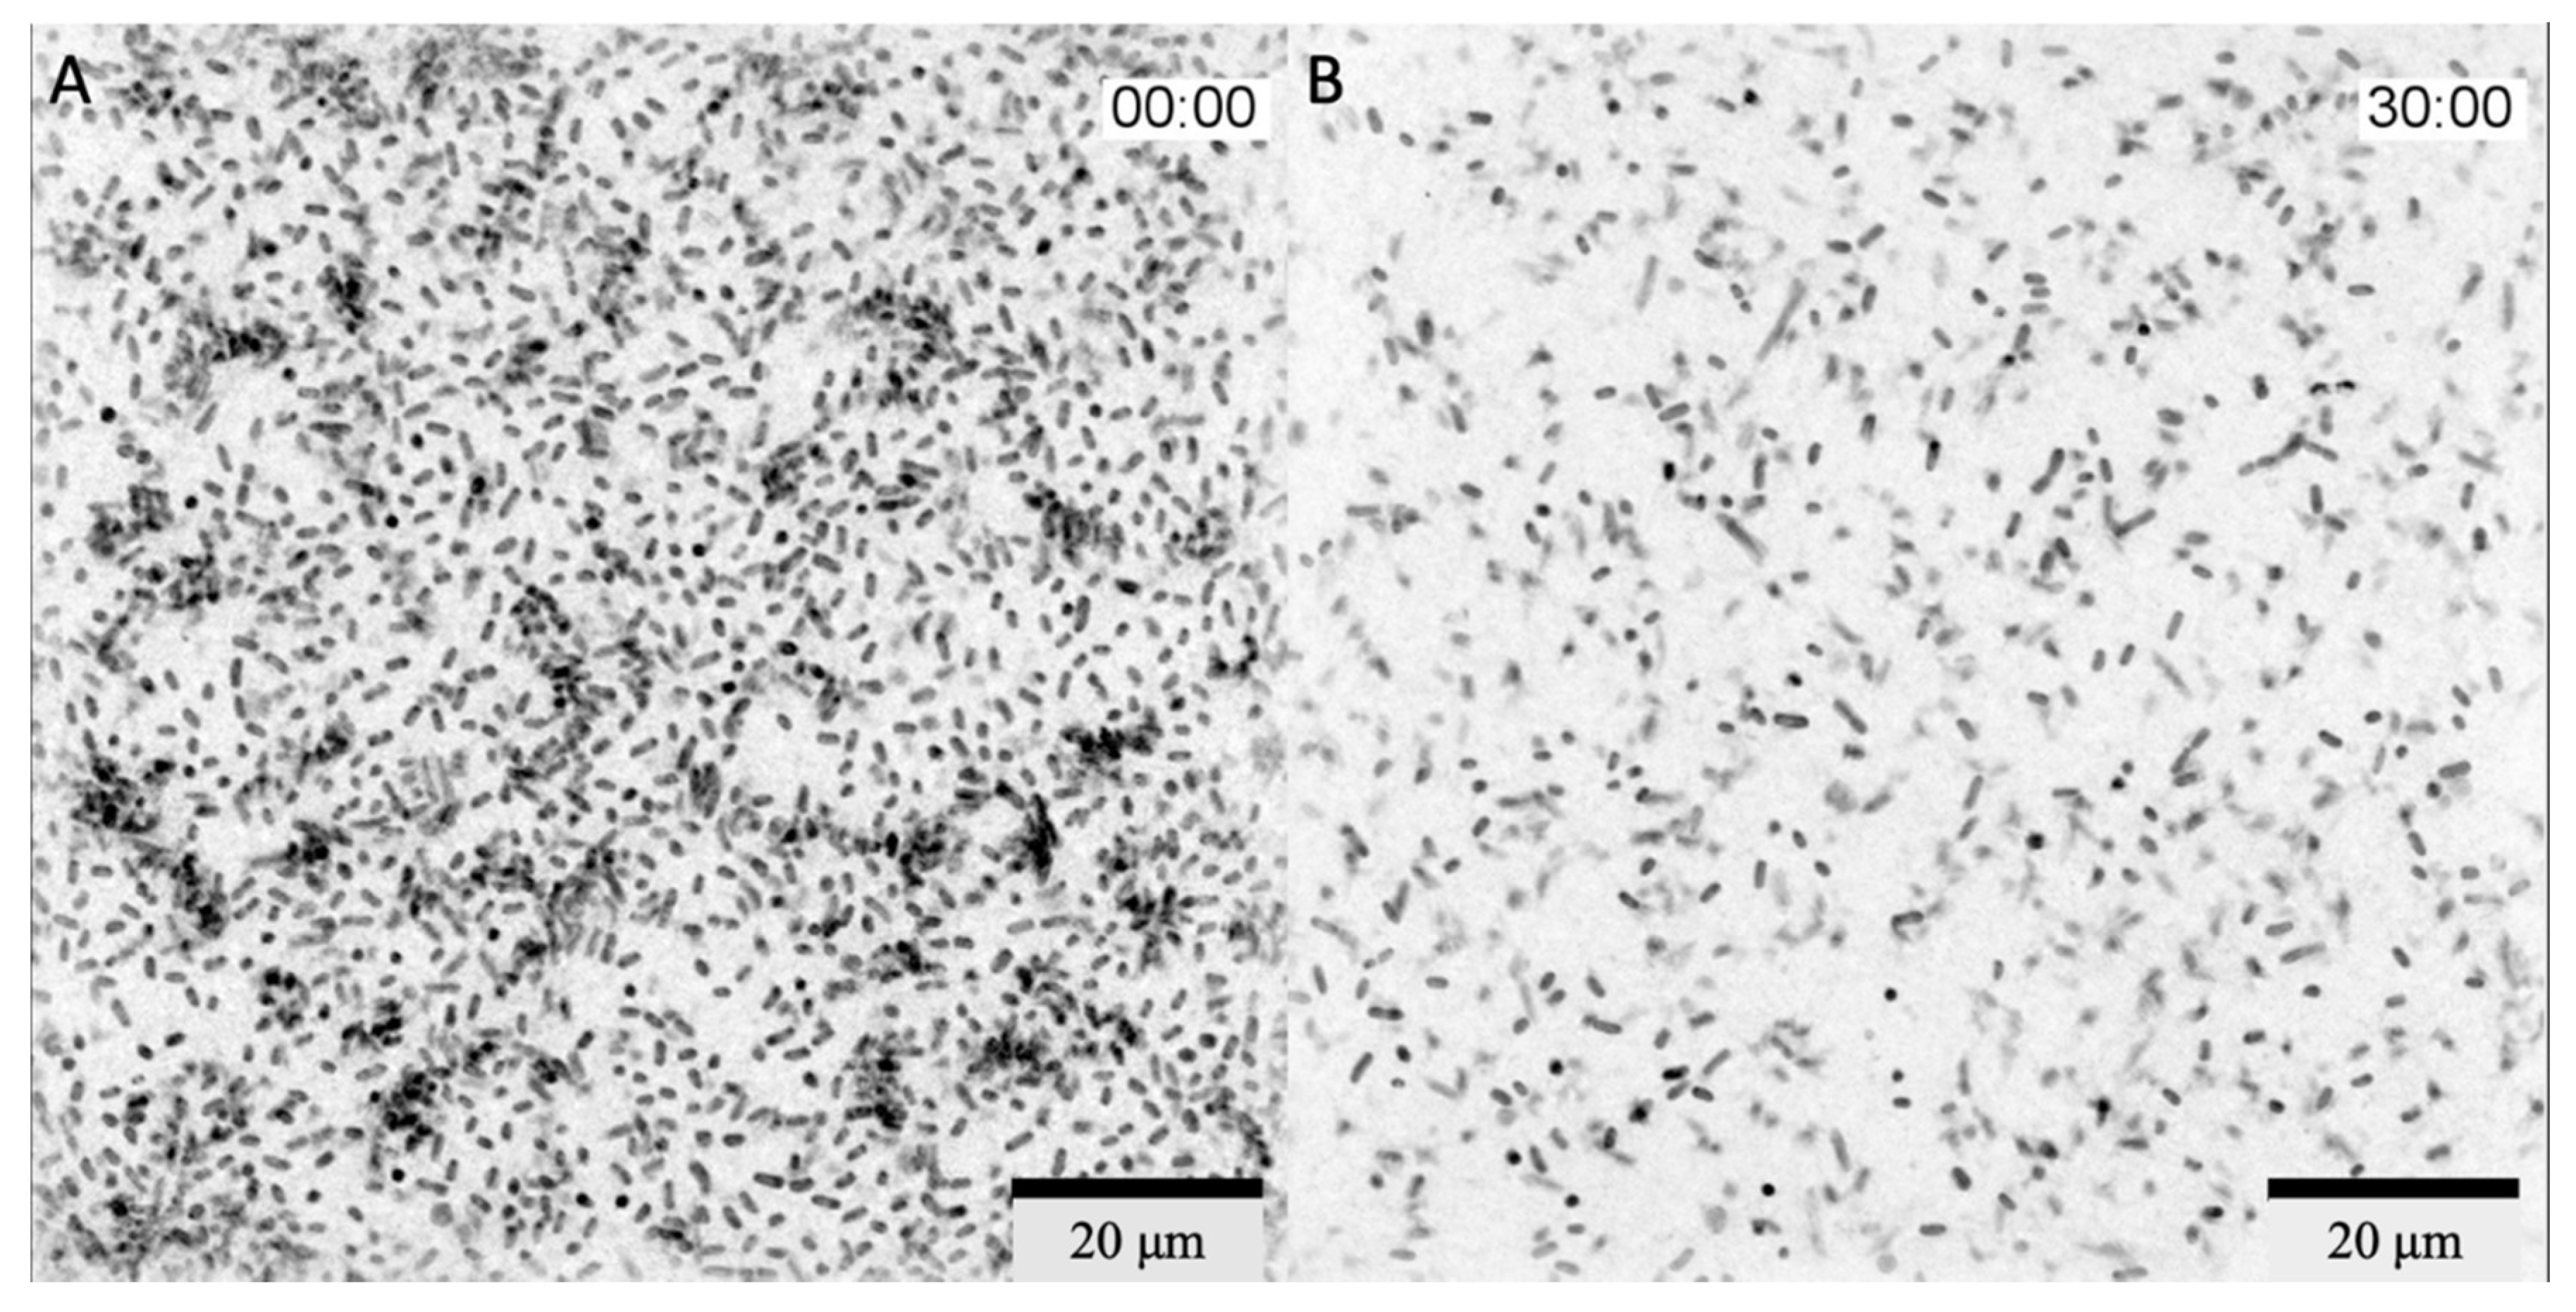

The bacteriophage cocktail was added 1 h 40 min after the start of the incubation and filming. Within 2 h 30 min after the addition of phages, there was a slight decrease in the number of bacteria in the field of view but formed bacterial microcolonies were still visible. Active reduction in the number of bacteria in the field of view started 2 h 30 min after the addition of the bacteriophage complex, and within 30 min, all microcolonies were disrupted (Figure 2). A full video of the bacterial lysis phase is provided in Supplementary Video S2. Additionally, a lysis of the bacterium adhered to the glass in the center of the microscope field of view was captured (Supplementary Video S3).

Figure 2.

3D Cell Explorer micrographs of K. pneumoniae (Kl 315) culture: (A) 2 h 30 min; (B) 3 h after the addition of the bacteriophage cocktail. Magnification ×58, scale bar 20 µm. The experiment was conducted in one repetition.

There was a decrease in the area covered by bacterial cells from 27.9% to 10.5% (Figure 3).